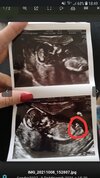

Super! 😍 Ja też na tym Twoim USG chyba widzę siusiaka. 😂 Za kilka dni będziesz miała pewność na 100%. 😊

Właśnie w tym sens, że na żadnym zdj nie ma 🙈 jeśli myślisz o tym samym zdj co ja to pani doktor powiedziała mi, że to akurat pępowina 😂 nie zrobiła akurat wtedy zdj i wgl był problem, żeby dojść właśnie tam 😂 pukała nawet delikatnie sprzętem w mój brzuch żeby się okręcił😁

Jakby miała zgadywać to tutaj. 😂

Też to widzę ale to chyba nie to 😂 uwierz mi, że przesortowałam neta i czasem babki pisały, że dziewczynki a ja widziałam siusiaka ale często pępowina i nóżki robią złudzenia 🙈 na moje też powiedziałabym, że to siusiak 😂 jestem ciekawa czy pani doktor dobrze widziała 🤔